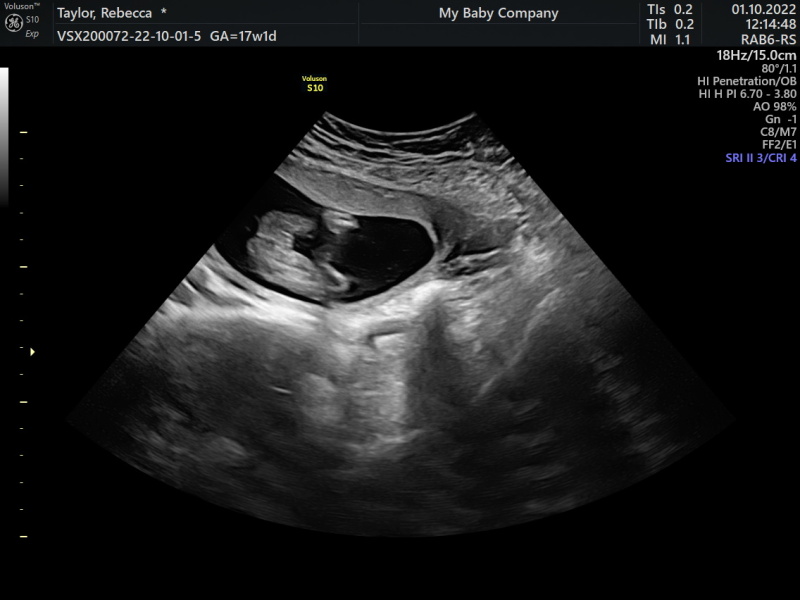

Hey x i had a private scan at 17 weeks, asked them to put sex in an envelope, opened it and it was a boy. Since then i wanted reassurance and asked for potty shot (which i have attached)... I then questioned the sex and said are u sure its a boy and she said no its a girl? So im massivly confused.. What's everyone think? I got a free rescan with the place later today so ill let u know the outcome... But yes think they may have got mine wrong i dont know?

That’s a girl i can see three lines and nothing sticking out

@Bectay35x your potty shot image looks very girly to me, I'll attach mine just so you can see the difference. At least they're offering you a rescan for reassurance x